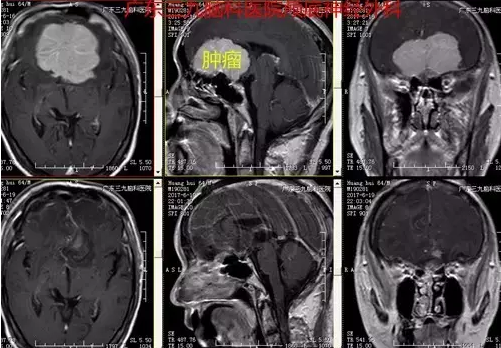

图4:术后术后磁共振提示肿瘤全切

本例患者为老年男性,病程长,以头晕头痛就诊,伴恶心呕吐,未有明确定位症状,易误诊,行头颅CT及MR检查提示前颅窝底脑膜瘤。临床辅助检查中,头颅MR扫描对前颅窝底脑膜瘤的诊断意义最大。MRI 检查不仅可以显示肿瘤的体积及具体起源部位,而且还可以清楚显示肿瘤与邻近重要结构,如视神经、颈内动脉及其分支、垂体柄、下丘脑等的关系,这对指导手术人路的选择具有重要的意义。多数情况下前颅窝底脑膜瘤的MR增强扫描可见较均匀一致的强化,这与脑膜瘤的血运较丰富有关,有的情况下,如果肿瘤增强十分明显,而且肿瘤瘤内或周边有较多的血管流空,多提示肿瘤的供血血管较多,肿瘤血运丰富。本例患者术前CTA提示其内血供丰富,双侧大脑前动脉受压明显向右侧偏移,MR增强明显,其内见较多流空影,大小约5.9×6.3×3.5cm,体积巨大,且与嗅沟、视神经、垂体炳、下丘脑等关系密切,手术难度较大,术中行冠状切口经额予以全切除,切除时间约半小时,术中出血少,术后患者恢复快,术后严格监测血离子、尿量、垂体激素等的变化,术后患者出现一过性精神症状,目前恢复良好出院。